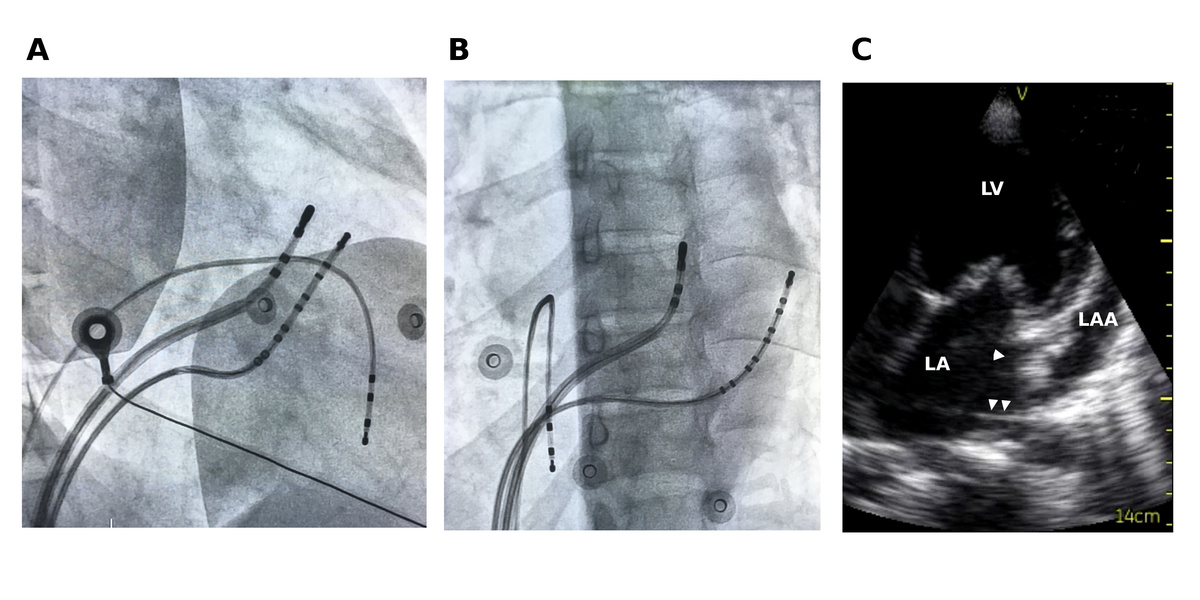

Appendage pathways

• RAA to RV

• LAA to LV

• Endocardial ablation from within AA may be difficult

• Epicardial approach may be required

• Proximity of major coronary arteries to LAA

appendage_3d.png

Nikola Dragisic, MD, FACC, Emily R. Backes, MD, Lindsey Malloy-Walton, DO, MPH, Philip M. Chang, MD, FACC, FHRS. Atrial appendage accessory pathway ablation: Tips for recognition and approach to ablation. Heart Rhythm Case Reports, Vol 9, No 12, December 2023 876